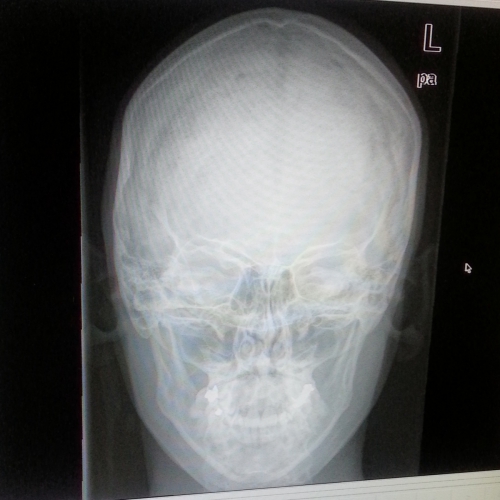

No, Tako je napisal napotnico za rentgen glave, ki sem ga opravila že danes ter odvzem krvi, ki sem ga tudi že imela danes. naročil je teste tumorskih markerjev, v ponedeljek pa dobim datum še za scan skeleta, saj sem bila danes prepozna, ker delajo le do dveh. Kri sem tako oddala, potem pa odšla na rentgen. Ker jaz kot jaz ne morem biti tiho, sem bogemu revežu, ki je rentgen opravljal, postavila 100 in eno vprašanje. Vedel ni pa nič. Tako mi je rekel, da bom vse odgovore dobila, ko bo zdravnik dobil moje slike v vpogled. Brazda se je na bočni sliki sicer videla na frontalni pa ne. Ker moram imeti vse dokumentirano, sem poslikala tudi slike, ki so nastale. Fotke so tako super, da sem že rekla, da bo ena pristala na moji profilni sliki na Facebooku. :)